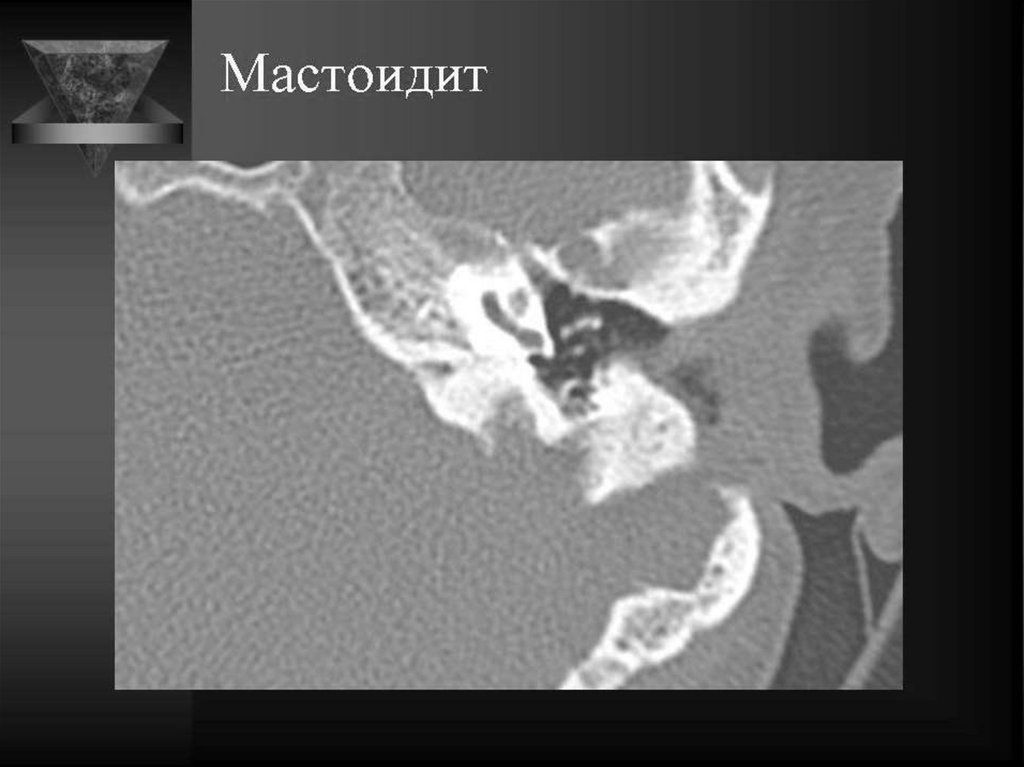

29. ОСТРЫЙ ОТОМАСТОИДИТ

Острый мастоидит,

субпериостальный

абсцесс

30. Субпериостальный абсцесс

31. ОСТРЫЙ ОТОМАСТОИДИТ

Острый

мастоидит,

мозжечка

32. Зигоматицит

33. ОСТРЫЙ ОТОМАСТОИДИТ

Тромбоз сигмовидного синуса

34. Мастоидит, синус-тромбоз, эпидуральный абсцесс